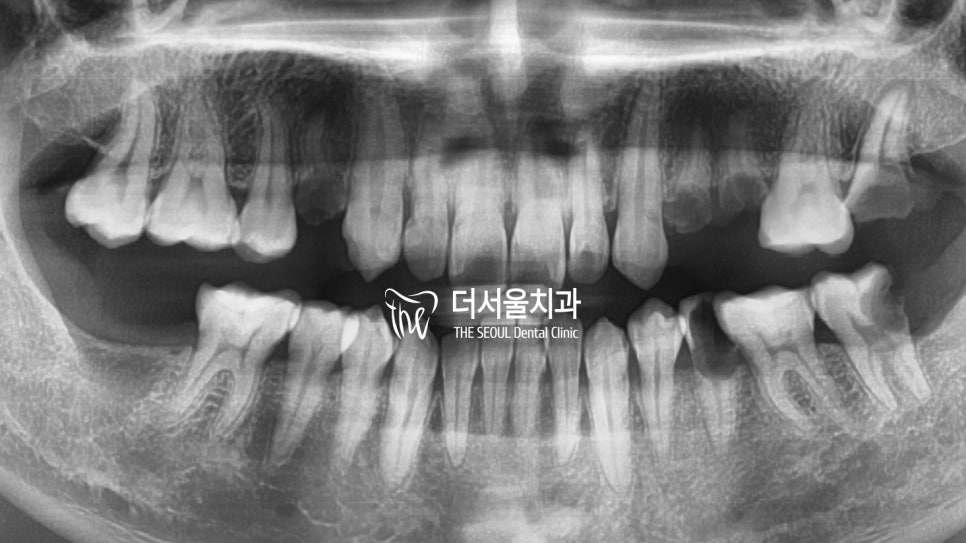

『부러진지 오래된 치아,

어떤 문제를 불러일으킬까?』

잔존 치근을 제때 치료하지 않고

그대로 내버려 두게 되면